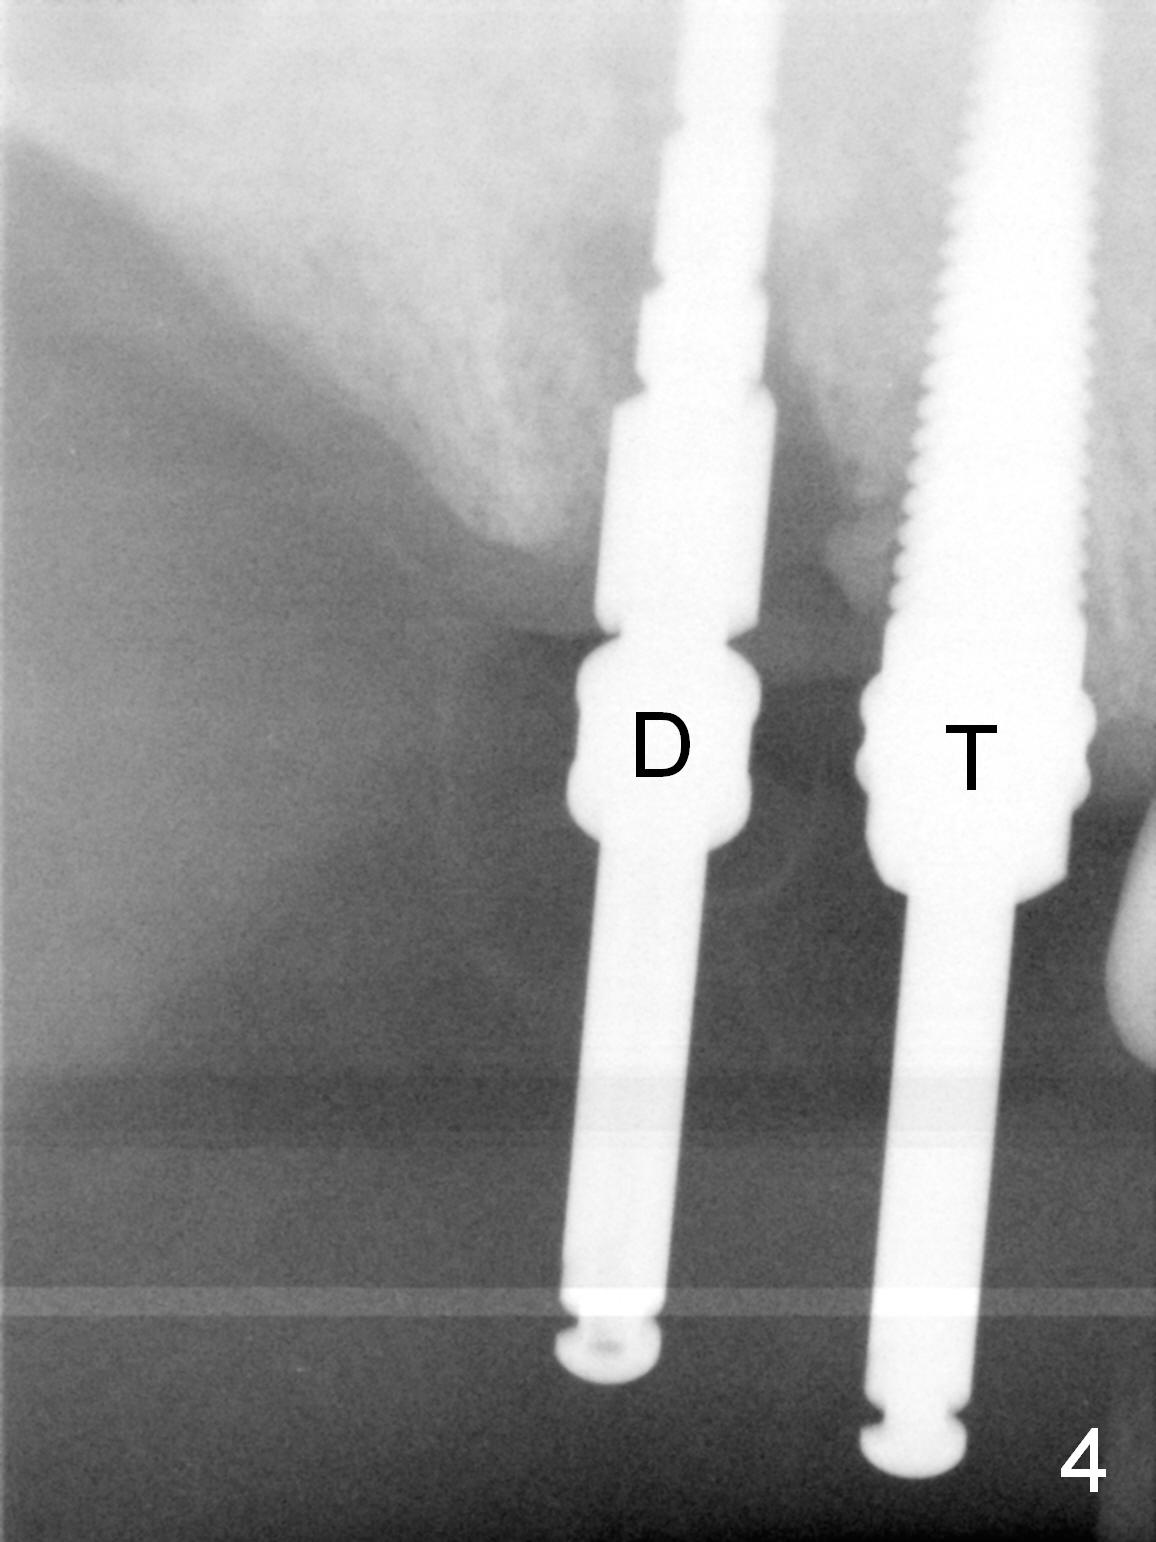

Several of CK's upper teeth (apparently in cross bite) are to be restored with implants (Fig.1).  The first two are #5 and 6; note the oval roots (Fig.2).  After extraction, and curettage, osteotomy starts in the palatal aspect of each socket.  The 1st intraop PA shows that the trajectory at #6 is incorrect (Fig.3).  After adjustment, osteotomies look parallel (Fig.4: D: 3.5x20 mm drill; T: 4.5x20 mm tap).  This suggests how important it is to use parallel pins to check initial osteotomies for neighboring implants (Fig.3).  The trajectory of the implants remains acceptable (Fig.5: 4.5x20 mm with insertion torque »60 Ncm); so is the position of the implants (as palatal as possible; Fig.6 (*: bone graft)).   Immediate provisionals are fabricated in cross bite.